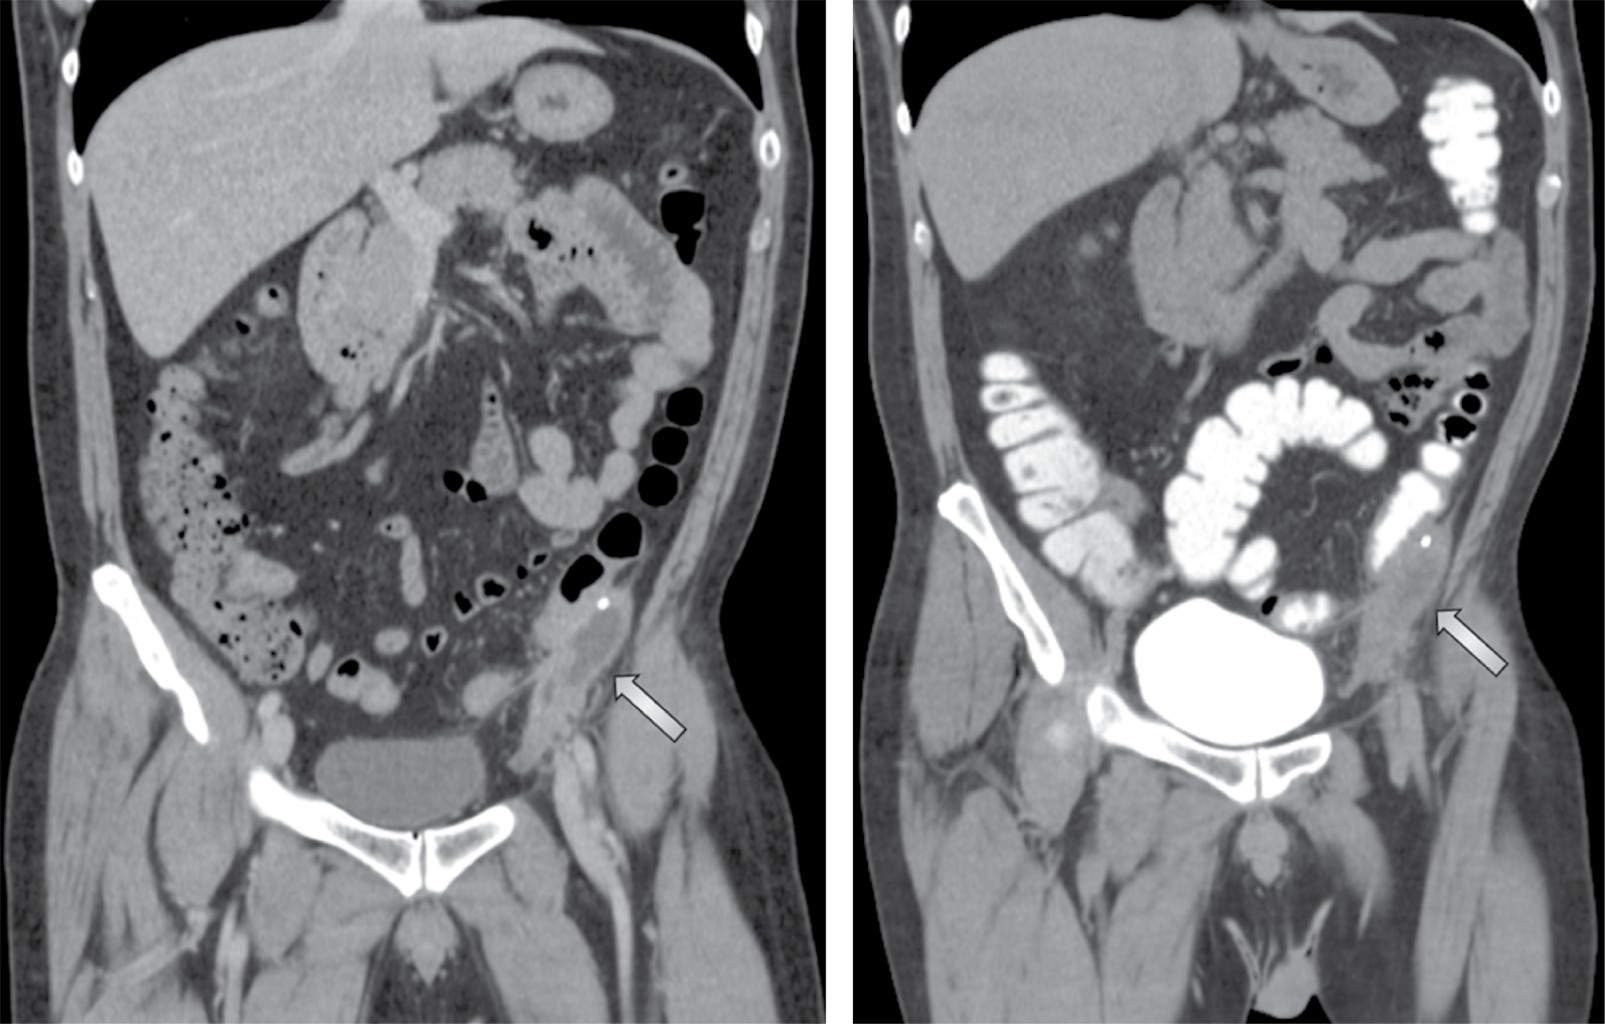

Paciente masculino de 54 años quien inició el 20 de abril de 2020 con dolor abdominal de predominio en fosa iliaca izquierda; se solicitó estudio tomográfico y se estableció el diagnóstico de diverticulitis aguda grado Hinchey Ib (absceso pericólico) en otra clínica y se manejó con ceftriaxona 1 g intramuscular cada 12 horas por cinco días. Dos semanas posteriores al término del tratamiento presentó exacerbación del cuadro con incremento del dolor y alza térmica cuantificada hasta 37.7 oC, sin otra sintomatología acompañante. Como comorbilidades refirió únicamente trastorno depresivo mayor en tratamiento con clobazam. Como antecedente de importancia destacaba plastia inguinal izquierda con colocación de malla por vía laparoscópica dos años previos al inicio de los síntomas. A la exploración física sus signos vitales eran presión arterial (TA) 130/80 mmHg, frecuencia cardiaca (FC) 90, frecuencia respiratoria (FR) 16, temperatura 37.1 oC; abdomen blando, depresible, doloroso a la palpación media y profunda de fosa iliaca izquierda, sin datos de irritación peritoneal y sin cambios en la coloración de la piel. En los estudios de laboratorio de ingreso: leucocitos séricos 6.2 × 103/μL, neutrófilos absolutos 4.22 × 103/μL, proteína C reactiva ultrasensible 3.06 mg/dL, velocidad de sedimentación globular 36 mm/h y procalcitonina sérica 0.05 ng/dL. Una tomografía de abdomen reveló una colección hipodensa localizada en receso paracólico izquierdo (Figura 1), cuyas características tomográficas eran sugestivas de un proceso infeccioso. Tras la administración de contraste endovenoso y transrectal se observó reforzamiento de la pared de la colección sin evidencia de comunicación entre la colección y el colon (Figura 2). Se realizó drenaje percutáneo de la colección guiado por tomografía obteniendo 10 mL de material hematopurulento dejando catéter Dawson Mueller 8.5 Fr; el cultivo aeróbico reportó crecimiento de Serratia marcescens sensible a carbapenémicos. Completó cinco días de tratamiento con meropenem 1 g intramuscular cada ocho horas y fue egresado previo retiro del drenaje. Reingresó tres semanas después de su egreso para el retiro de la malla. Realizamos un abordaje en línea media infraumbilical, incidiendo hasta el espacio preperitoneal sin entrar a cavidad (Figura 3). Se disecó el espacio preperitoneal izquierdo de forma roma hasta el nivel de la espina iliaca anterosuperior ipsilateral, visualizando y respetando los vasos epigástricos profundos, mismos que se rechazaron superiormente junto con fibras del recto abdominal (Figura 4). Se extrajo malla de poliéster autoadherible, la cual se encontraba plicada y distorsionada (Figura 5). Por último, se lavó el espacio preperitoneal con un litro de microdacyn, se colocó drenaje cerrado 19 Fr, se afrontó aponeurosis anterior con surgete tipo Small bites utilizando sutura 0 de muy lenta absorción y se colocaron grapas en piel. El procedimiento se llevó a cabo en un tiempo de 60 minutos y un sangrado cuantificado en 30 mL. Cursó su postoperatorio sin eventualidades y fue egresado al día siguiente. El drenaje se retiró a los cinco días en consulta externa.

Figura 1

Figura 2